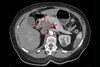

What pathology is seen here?

Hepatocellular Carcinoma (HPC) ## Footnote Arrow: Border between the tumour and the rest of the liver White arrow: Cyst

243